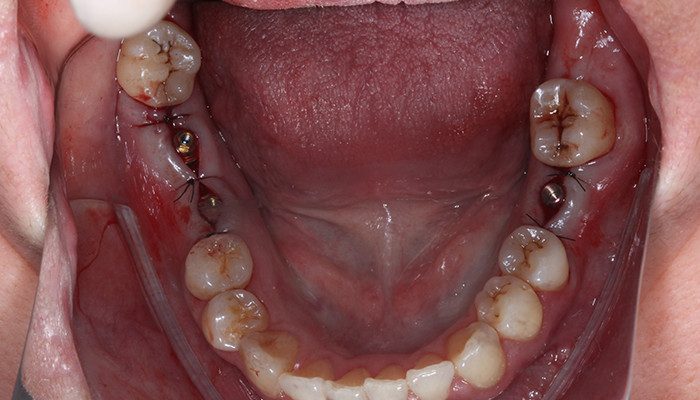

Após instalação e torque de instalação final (32 N.cm para Pilar e 20 N.cm para Mini Pilar) foi suturado e escaneado com Scanner Dexis 3700. Após a primeira impressão digital foi duplicada a malha e apagadas na cópia as regiões dos implantes para aquisição dos scan bodies Aikkon. Em seguida foram removidos os corpos de escaneamento e os intermediários protegidos com coifas de proteção Aikkon e a paciente instruída dos cuidados pós opera tórios e liberada.

14 | Intermediários Aikkon instalados e sutura realizada.

15 | Scan bodies Aikkon instalados.